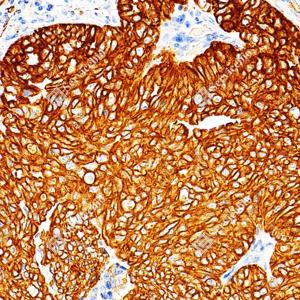

IHC检测Cytokeratin 18蛋白(货号 GB15232). 样品: 人肺癌, 4%多聚甲醛 (货号G1101) 固定12-24小时. 抗原修复: 柠檬酸抗原修复液(干粉, pH 6.0) (G1201), 高压锅均匀喷气计时2分钟. —抗: 1: 500稀释, 4℃ 孵育过夜. 二抗: S-vision免疫组化多聚二抗(山羊抗小鼠), 即用型(货号G1301), 室温孵育20分钟. |